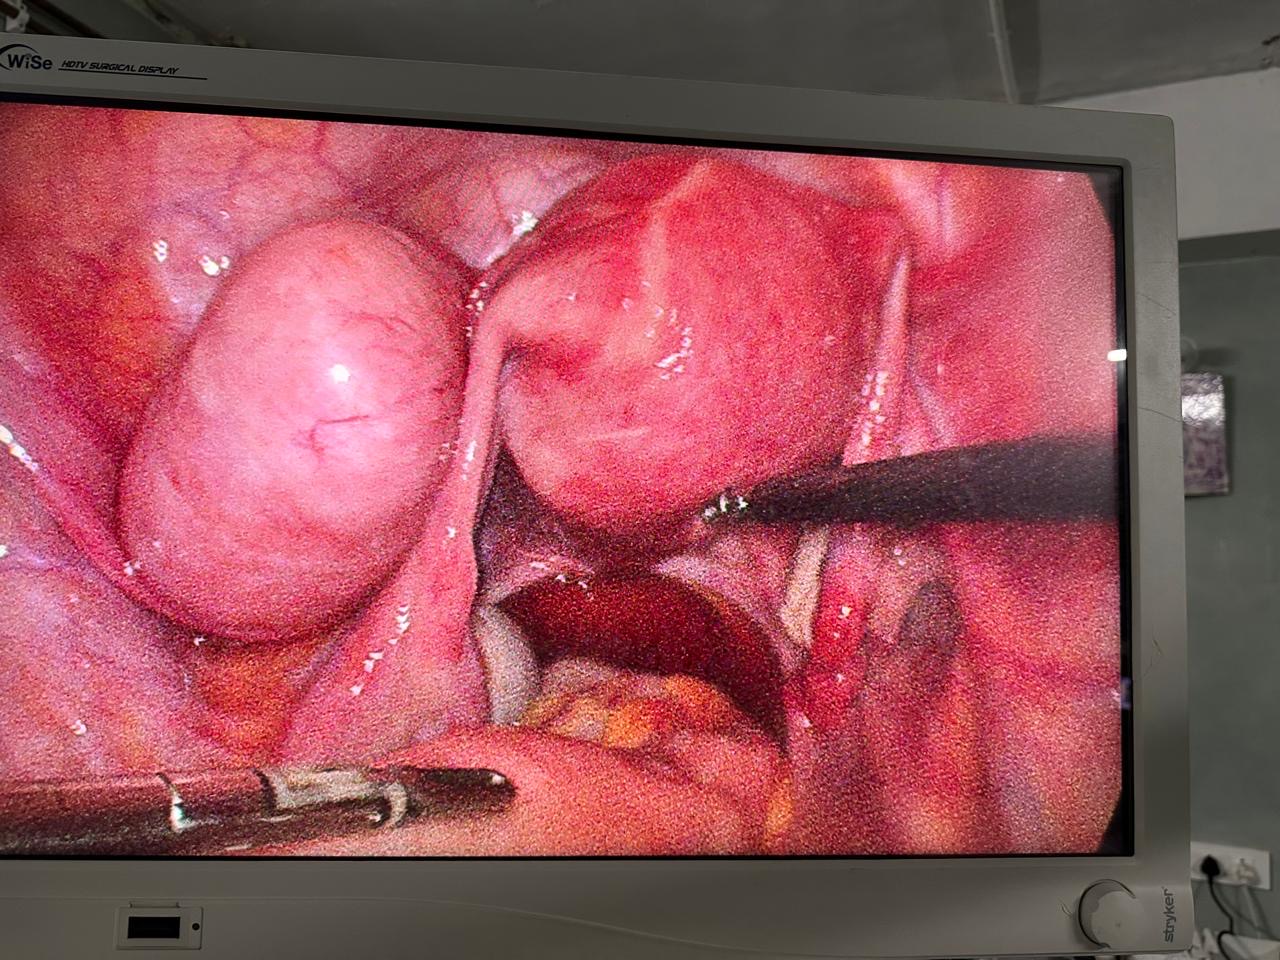

Laparoscopic and minimally invasive gynecological surgeries offer advanced, safe, and effective solutions for diagnosing and treating various reproductive health conditions. These procedures involve small incisions, specialized instruments, and a high-definition camera, allowing surgeons to operate with precision while minimizing pain, scarring, and recovery time. Commonly used for conditions such as ovarian cysts, fibroids, endometriosis, and ectopic pregnancies, these procedures provide quicker recovery and improved outcomes compared to traditional open surgery.

Advanced Surgical Technology

We use state-of-the-art equipment for high-precision, effective, and safe surgical outcomes.